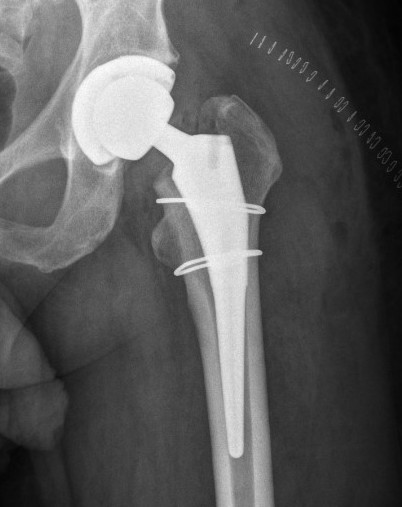

Femoral Fracture

Management

Cerclage wires

+/- bypass fracture with longer stem

+/- plate